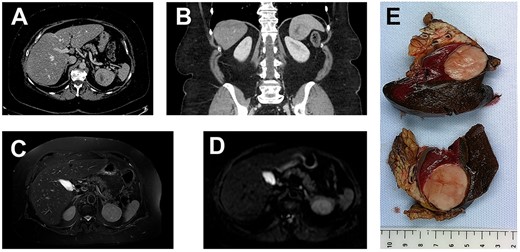

A 69-year-old woman presented to the hospital in the context of surveillance for sigmoidian diverticulitis. A Computed Tomography (CT) scan was performed and a splenic mass was found incidentally. It was absent on the previous CT scan performed 12 months earlier. The mass was solid and it was located at the splenopancreatic border (Fig. 1), without specific characteristics on Magnetic Resonance Imaging (MRI) and not hypermetabolic on PETscan. The patient had a history of a treated breast cancer, so the first hypothesis was that of a metastasis of breast carcinoma. A biopsy was performed which showed necrosis and massive inflammation consisting of plasma cells and lymphocytes, with no epithelial cells. The patient was in a good general state. Blood tests related to a possible infection were negative. The C-reactive protein was elevated (8 mg/L). The final decision was to perform a splenectomy and caudal pancreatectomy.

(A, axial) and (B, coronal), portal venous phase CT-scan showing a 43×40×39 mm lesion of the inferior pole of the spleen. The lesion is heterogeneous with a center of necrotic appearance, without calcification and enhancement after injection of the contrast product.

A well-defined splenic lesion with high signal intensity on T2-weighted (C) and diffusion-weighted (D) MRI.

(E) The macroscopic appearance: tumor is solid, yellow-tan on cut surface with well-circumscribed borders.

Grossly, the dimensions of resected spleen were in the right range. The tumor measured 6 cm in diameter; it was gray-whitish with areas of necrosis (Fig. 1). It was encapsulated and localized inside the splenic parenchyma with ‘pushing margin’ effect toward the pancreas without invading it.